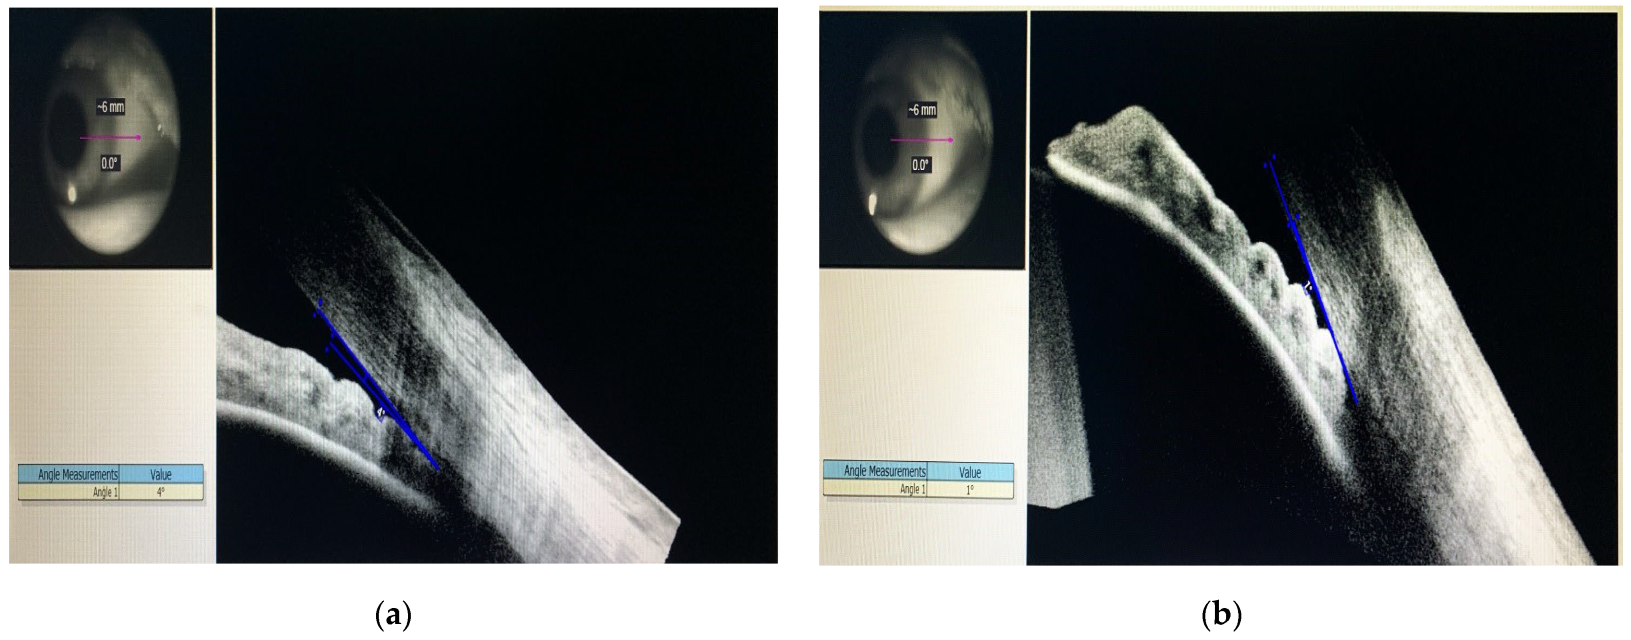

Gonioscopy showed angle closure in both eyes, supported by the anterior segment OCT that revealed a 4 degree closed angle in the right eye and a 1 degree closed angle in the left eye (Figure 2a,b).

Figure 2.

Gonioscopy in both eyes, supported by the anterior segment OCT: (a) Right Eye; (b) Left Eye.